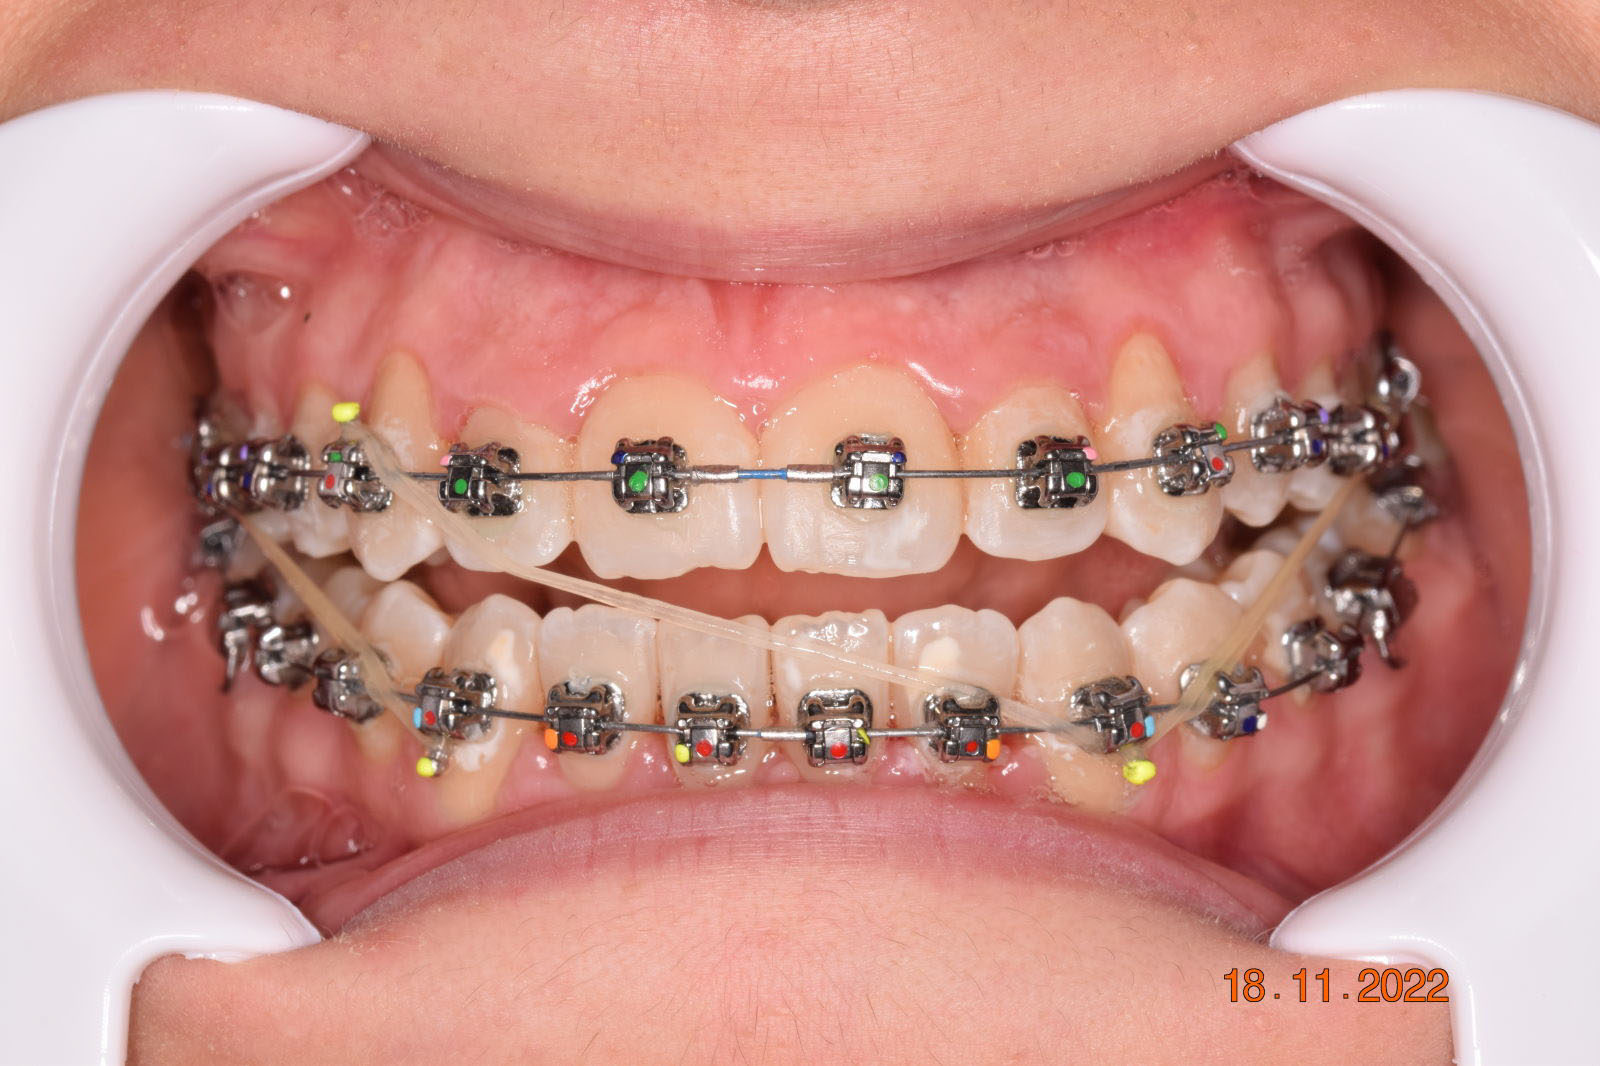

The treatment began in 2017. Given the patient’s preference for less visible brackets, Damon Clear brackets were selected. High torque upper cuspids and low torque upper incisors were chosen to offer the best torque control for upper arch development. For the lower arch, there were no alternative bracket configurations available. Bite turbos were applied to the upper second molars.

Adhering to the principles of Face First Orthodontics, the primary objective was to increase midface support by expanding the upper maxilla, fixing the cross bite, and aligning the teeth. Closing the open bite was a secondary objective.

Dr. Coca’s treatment plan followed the Biology First Orthodontics approach, which aims to minimize biological interventions. The treatment plan avoided extractions, stripping, TADs, corticotomy, and RPE. Given the facial requirements, a non-extraction treatment option was chosen.